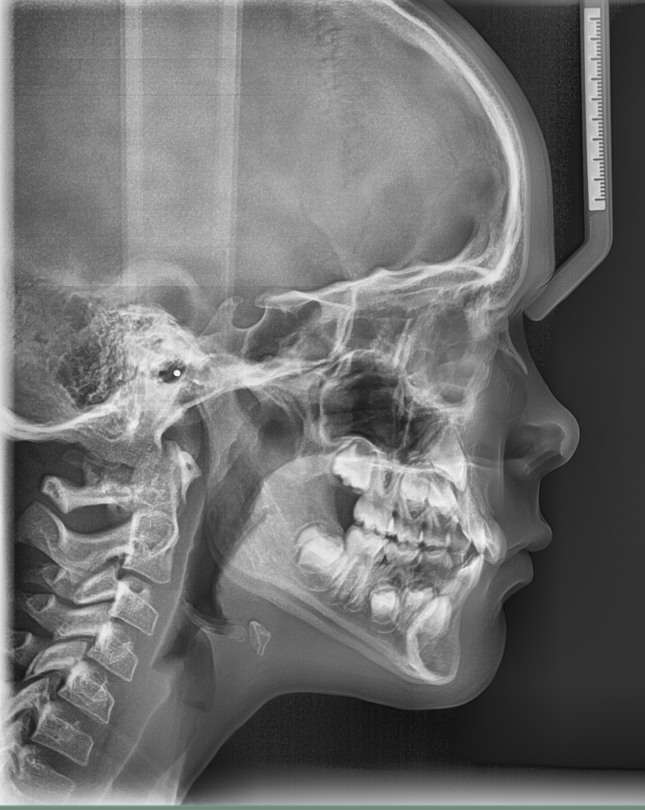

TREATMENT STARTED AT AGE : 9

- Myobrace K1 Medium

- Mixed Dentition

- Class 2 Div I

- Moderate